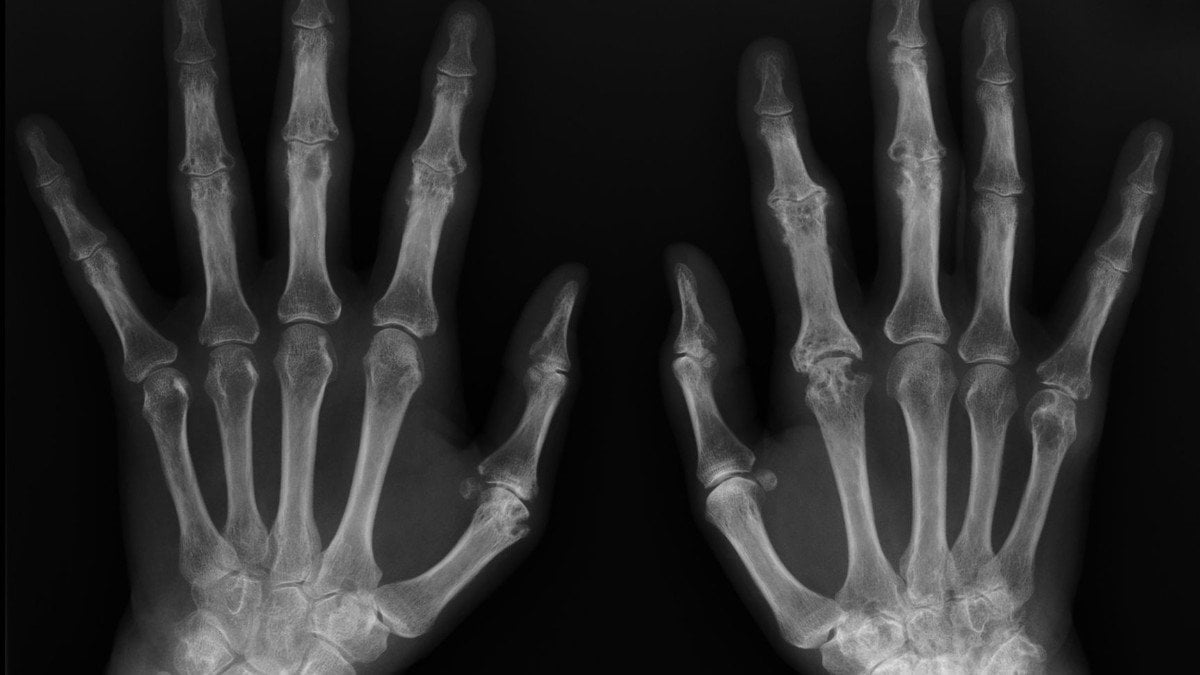

Bebeklikten Yetişkinliğe Ellerimizin X-Işını Görüntüsü ve Kemik Yaşı

Aşağıda gördüğünüz, bir insanın bebekliğinden yetişkinliğine kadar farklı zamanlarda çekilmiş ellerine ait X-Işını Taraması (X-Ray) görüntüleridir.

Bir çocuğun kemiklerinin uçlarında (örneğin parmak ve bilek kemiklerinin uçlarında) "büyüme bölgeleri" olarak da bilinen "büyüme plakaları" bulunur. Bu bölgelerde kemiklerin boylamasına uzamasını sağlayan özelleşmiş hücreler vardır. Bu büyüme plakalarını X-Işını Taraması altında görmek kolaydır, çünkü daha yumuşak yapılıdırlar ve içeriklerinde daha az mineral vardır. Bu da, X-Işını altında diğer dokulara göre daha koyu gözükmelerine neden olur. Görselde, "A" olarak işaretlenmiş fotoğraftaki kemikler arası siyah boşluk bundan kaynaklanır.

Çocuklar büyüdükçe, büyüme plakalarının görünümü de değişir. Giderek daha ince hale gelirler, buna bağlı olarak X-Işını Taraması'nda daha beyaz (yani diğer kemikler gibi) gözükürler ve hatta sonunda tamamen görünmez bile olabilirler. Artık büyük oranda veya tamamen yok olmuş bu plakalara "kapanmış büyüme plakaları" adı verilir. Her bir yaşta farklı gözüktükleri için, sadece kemiklere ve büyüme plakalarına bakarak bir insanın kemik yaşı belirlenebilir. Bunun için doktorlar bir kemik atlasına başvururlar ve söz konusu bireyin plakalarının görünümünün atlastaki hangi kemik yaşına ("iskelet yaşı" olarak da bilinir) denk geldiğini tespit ederler. Böylece bireyin yaşı belirlenebilir.

Bir çocuğun kemik yaşı ile kronolojik yaşı (bizim basitçe "yaş" olarak bildiğimiz versiyonu) arasında eğer ki fark tespit edilirse, ortada bir kemik veya gelişim problemi olduğundan kuşkulanılabilir. Ancak bu mutlaka bir uzman tarafından analiz edilmelidir; zira kimi zaman sağlıklı bireylerde de kronolojik yaş ile kemik yaşı arasında farklılıklar görülebilir.